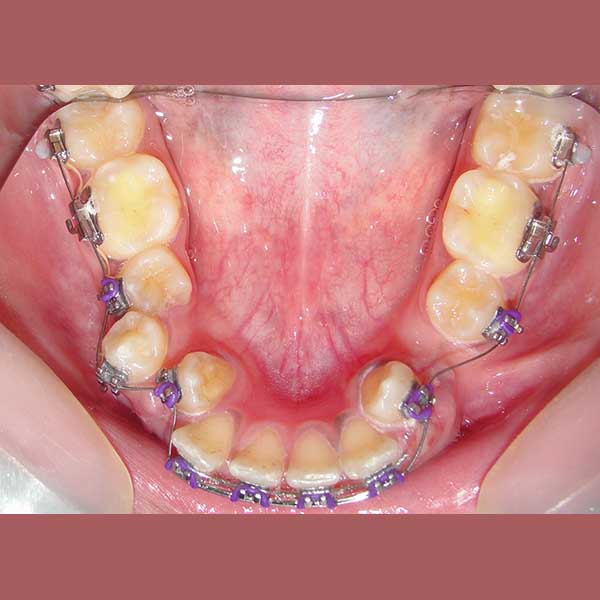

Case: Impacted upper canines – severe overlap – fixed orthodontics

By examining the case and taking X-rays, I observed the upper canines in her mouth, and an embedded lower premolar was observed too on the left side, I started the treat the case, but because of the old age of this lady, the upper canines and the left lower premolar did not erupt on their own after we extracted the temporary canines, and she had to pull them out by braces. As for the lower jaw; The canines were pulled back in place and the embedded premolar was orthodontically pulled.